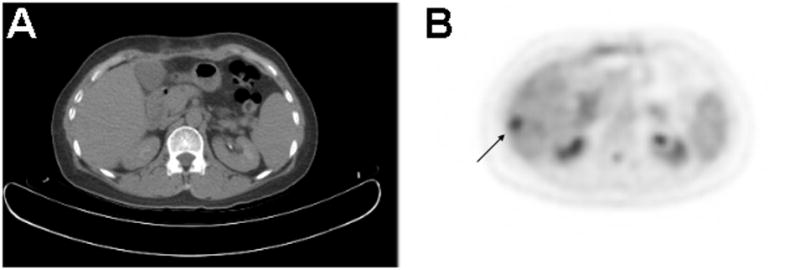

Figure 1.

PET/CT in a patient with hepatocellular carcinoma. A.) There is no evidence of liver tumor on the CT performed in tandem with PET, given that PET/CT is usually obtained without the administration of intravenous contrast. B.) On the FDG PET image, a 1.5 cm diameter hypermetabolic focus is seen in hepatic segment 6, corresponding to the primary malignancy. Diminished physiologic uptake of FDG resulting from chronic liver disease may have enhanced the conspicuity of HCC in this case. In general, the sensitivity of FDG PET for detecting HCC is sub-optimal due to physiologic FDG uptake by the normal liver

Ironically, the same reason that PET can discern tumor differentiation may also explain its poor overall rate of detecting primary HCC. Hexokinase and glucose-6-phosphatase is highly expressed in normal hepatocytes but in tumors may vary greatly depending on the degree of tumor differentiation. Consequently, tumors may not be readily distinguishable in the liver on the basis of glucose metabolism due to variable FDG uptake relative to normal liver tissue (Figure 1). This may account for the poor detection rates reported in a few studies8,13. Bohm et al13 compared PET with ultrasound, CT, and MRI, and found PET to be only slightly better than CT and US and inferior to MRI. Other studies have reported similar results in detecting HCC using PET (Table 1). There currently is little data on the variability of FDG uptake by normal and diseased liver tissue. Since 75% of HCC arise in the setting of chronic liver disease, it is important to understand how cirrhosis and other conditions may affect hepatocyte FDG metabolism, and consequently the diagnostic performance of FDG PET.